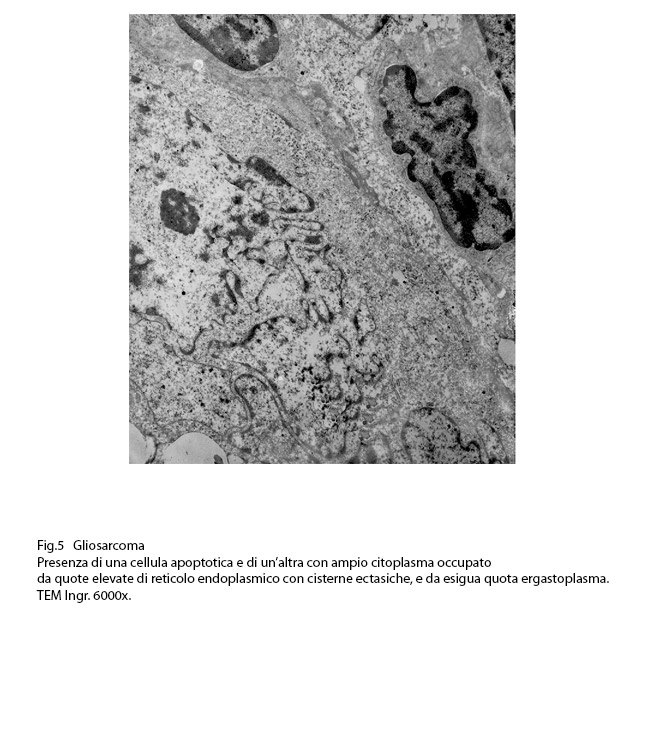

Fig.5  Fig.6

RETICOLO ENDOPLASMICO

Anche il reticolo endoplasmico mostra segni ultrastrutturali di stress sia in associazione all’ergastoplasma sia in situazioni univoche.

Infatti,si repertano cellule di gliosarcoma con l’ ampio citoplasma occupato quasi interamente da queste formazioni; esse sono molto numerose, si trovano tra loro adese e mostrano le loro cisterne ectasiche o micro cistiche, creando così in una visione panoramica una immagine di aspetto cribroso .Lo spazio interno alle cisterne è apparentemente privo di contenuto, o, più raramente, è occupato da materiale amorfo, debolmente elettropaco.

AUTOFAGOSOMI E AUTOLISOSOMI

L’autofagosoma è un focolaio vescicoloso endocellulare,di diverse dimensioni,di forma sferoidale,delimitato da una membrana a doppio strato;al suo interno si ritrovano materiali biologici eterogenei di aspetto granuloso,filamentoso,amorfo,tubulare e nei focolai voluminosi anche organelli citoplasmatici o frammenti nucleari.

Dopo questa fase di accumulo del cargo,segue quella della fusione tra l’autofagosoma e un lisosoma con formazione di una nuova struttura indicata con il termine di autolisosoma.